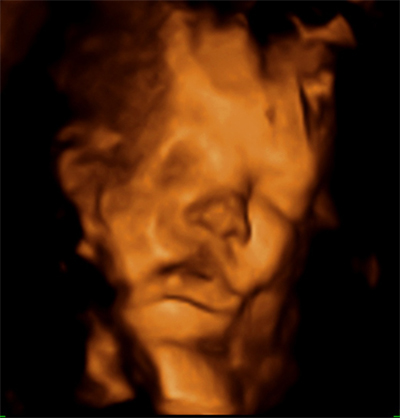

Ecografías con semanas de 35 de embarazo

¿Sabes que ahora también puedes hacerte una ecografía 5D, con una mejor definición de tu bebé y en la que el color de la piel del bebé es rosado en lugar de sepia? La ecografías que te mostramos a continuación son las diagnósticas ya conocidas en 3D:

Ecografía semana 35: cara de bebé. La imagen ecográfica en 3D nos permite ver con claridad la fisionomía de un niño de 35 semanas de gestación.